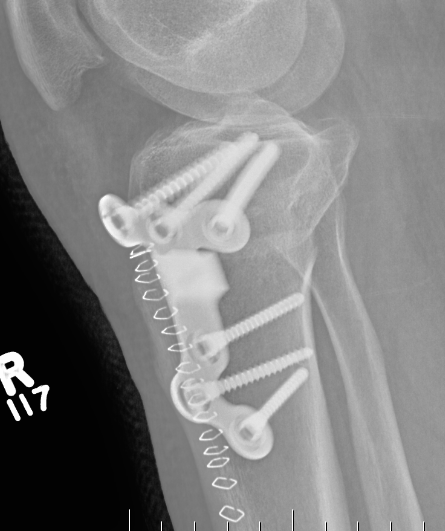

Stabilisation

- locking plates

- +/- autograft / allograft / synthetic bone graft

Arthrex Locking Puddhu plate PDF

Arthrex ContourLock system PDF